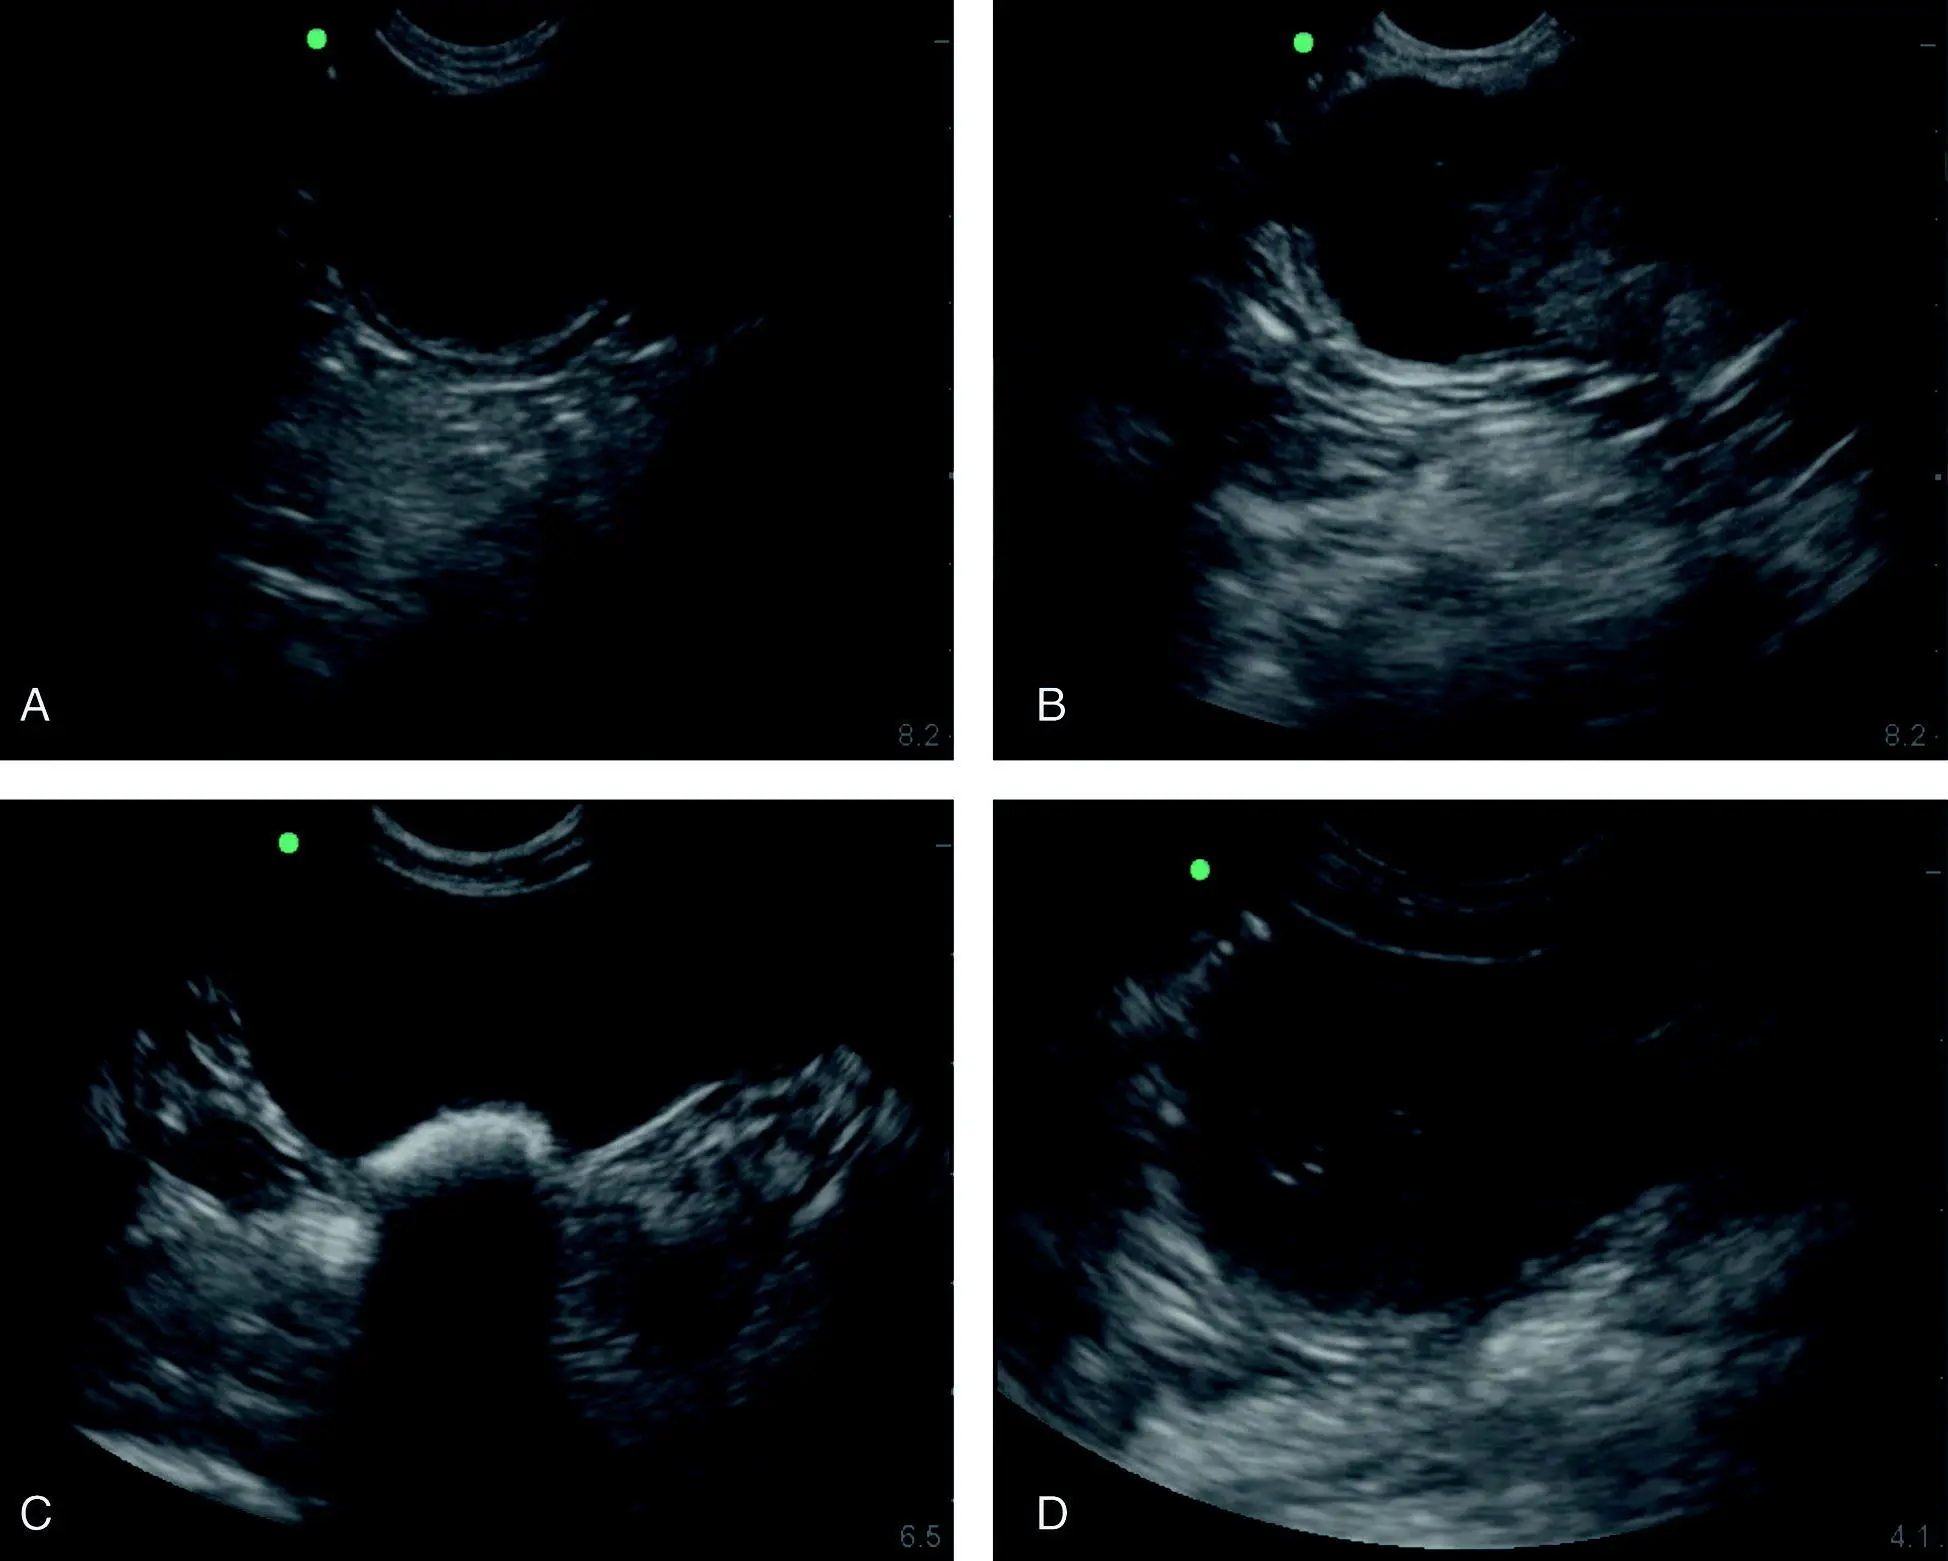

Figure 6.29. Pitfall of the thigh or a mass or other. In (A) and (B) are identical images unlabeled and labeled. The large circle encompasses the region of interest and its suspect origin of being the thigh muscle. The smaller circles are where typically the femoral artery and vein would be located with the patient in lateral recumbency and observing for pulsation or applying color Doppler would be helpful. The image shows how the thigh can push into the urinary bladder or stool in the colon or a caudal abdominal mass and make odd impressions when imaging the CC view with a patient in lateral recumbency. A digital rectal examination as part of a good physical examination with or without more advanced imaging is an ancillary evaluation to increase the probability of being correct. From the still B‐mode image, the exact origin of the circled structure may be unclear. UB, urinary bladder.

Source: Reproduced with permission of Dr Gregory Lisciandro, Hill Country Veterinary Specialists and FASTVet.com, Spicewood, TX.